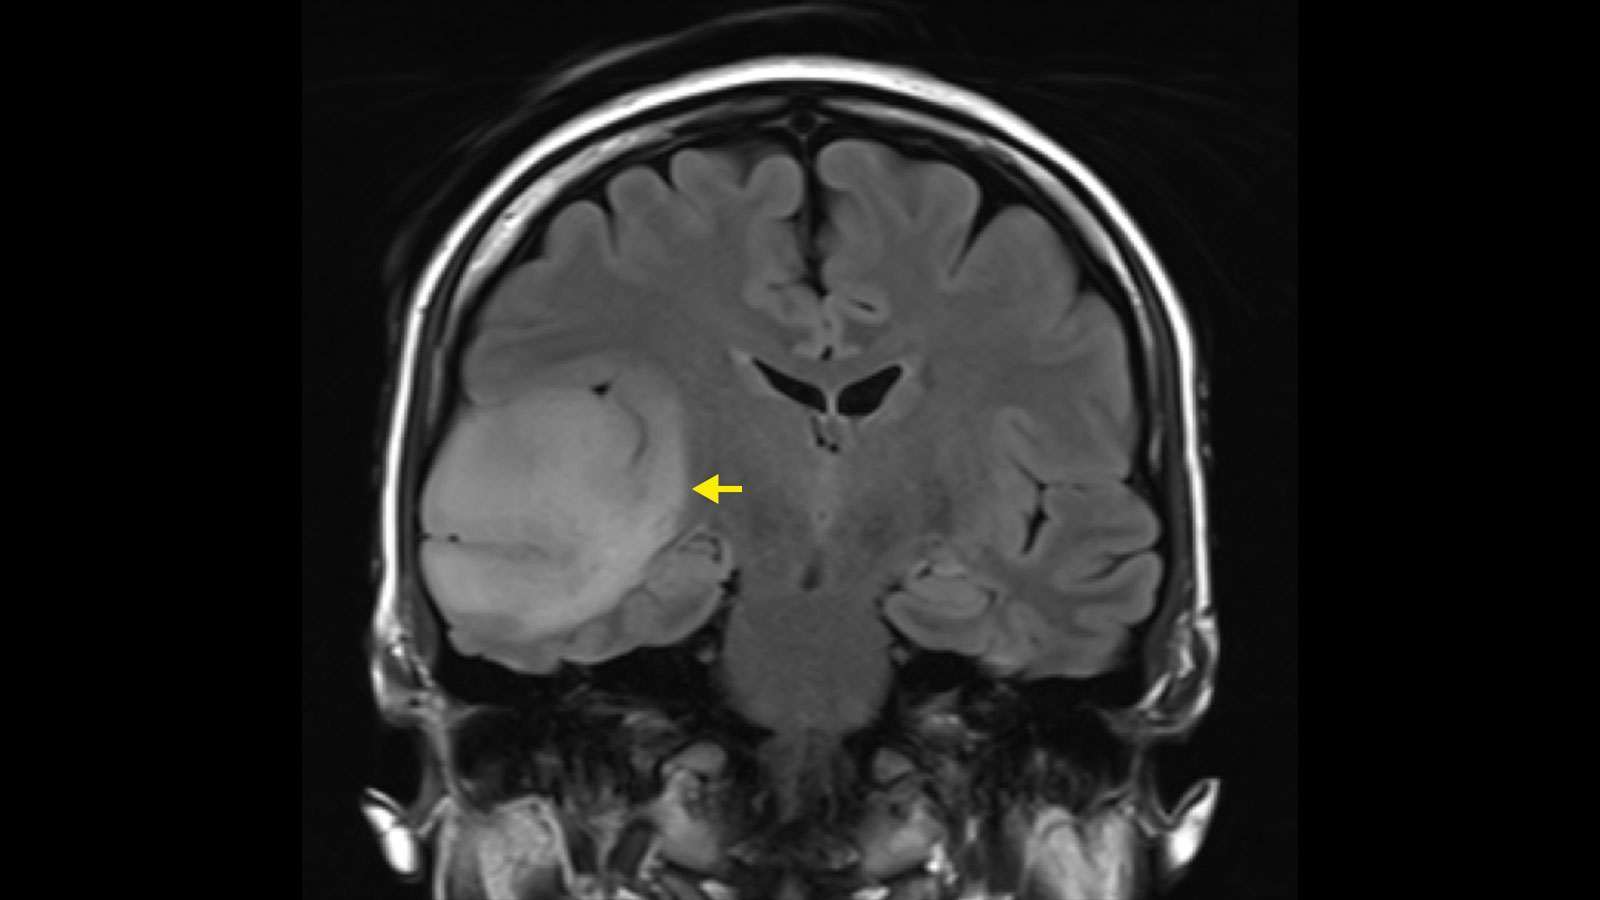

Основен етиологичен фактор за възникване на субарахноидален кръвоизлив е руптурата (или разкъсването) на съществуваща аневризма в мозъчните артерии. Аневризмата е балоноподобно (в литературата известно като „саково“) разширение на част от кръвоносния съд, чиито стени са изтънени и съответно по-застрашени от разкъсване при по-голяма сила на завихряне на кръвта.

Типично за аневризмалните сакове е, че в повечето пъти те са разположение по артериалните съдове в основата на мозъка. Причината за тяхното руптуриране обикновено е физическо или психическо пренапрежение, когато се създават условия за остро повишаване на кръвното налягане.

В поставяне на диагнозата главна роля заема лумбалната пункция – при негативни резултати от невроизобразителните методи (компютърна томография и ядрено-магнитен резонанс) нейното приложение е задължително.

Изследването на ликвор може да спомогне и за отдиференциране на диагнозата менингит, която дава сходни симптоми. Образната диагностика също е подходящ избор в диагностично-диференциален план. При болните в по-млада възраст е наложително да се направи мозъчна панангиография и то още в първите 24-48 часа от възникване на заболяването. Чрез това изследване може да се установят мозъчно-съдови малформации и дефекти (като споменатата аневризма), които се лекуват спешно по оперативен път.